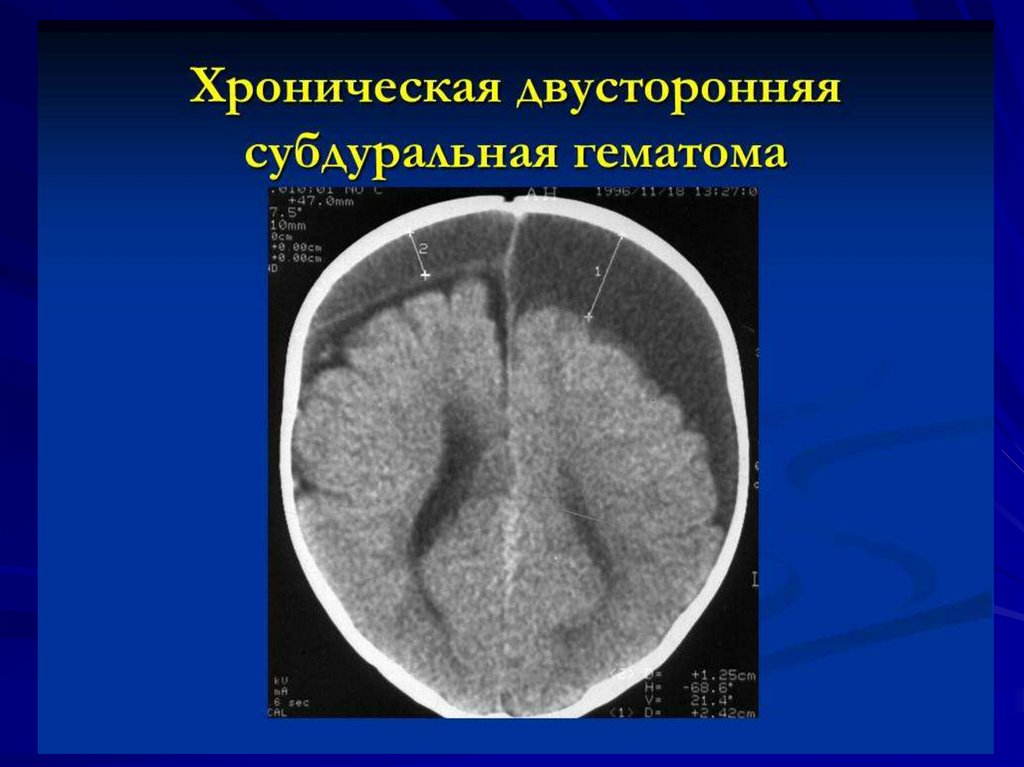

Внутричерепные кровоизлияния у новорожденных презентация - 92 фото